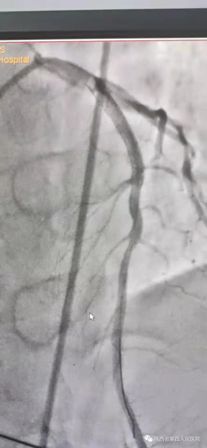

11月10日15时58分左右,家住21点基本策略 附近的中年男性辛先生在家人陪伴下来到我院急诊内科门诊诊室,满头大汗,捂着胸口说胸痛、胸闷、气短,急诊科主治医师钟高亮立即安排床位进行留观给予吸氧、心电监护、查体,心电图提示:1、窦性心律;2、室性早搏;3、急性下壁、前壁心肌梗死,诊断:急性冠脉综合征、心肌梗死。随后患者在急诊科留观室病情突然加重,意识丧失、四肢抽搐、面色苍白、全身大汗、呼吸急促,心电监护提示心室颤动,判断其可能为急性心肌梗死心源性休克,急诊科和心内科医生立即行胸外心脏按压,电除颤三次等对症治疗,立即启动胸痛患者抢救应急预案,开启绿色通道,和患者家属谈话,为其迅速办理入院手续,给予升压补液扩容等抢救治疗,积极完善术前准备,联系医务科和介入导管室,于16时22分将患者转运至导管室,心内科主任、主任医师王选琦带领团队副主任医师孙耀林、王崇振,主治医师马艳萍共同夺取患者最宝贵生命时间,为患者选择了从下肢股动脉穿刺造影,从穿刺到开通血管用仅仅只用了十一分钟。16时33分顺利完成PAG PCI支架植入术后成功再通,患者转危为安,随后入住心血管内科CCU病房继续治疗。

(术前造影) (术后)